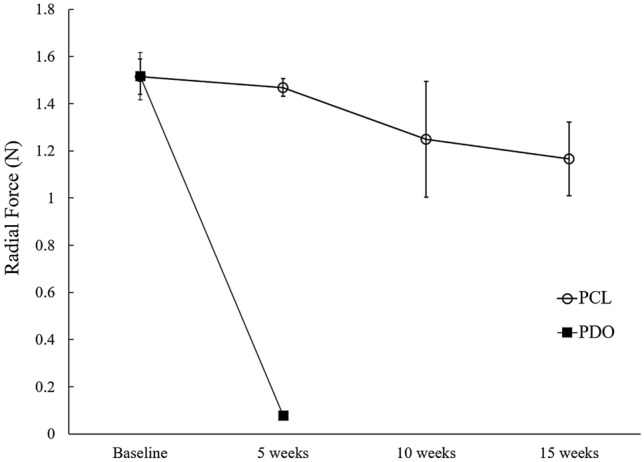

The mean radial forces of PCL stents after 5, 10, and 15 weeks in 37 °C normal saline were 1.47 ± 0.04 N, 1.25 ± 0.25 N, and 1.17 ± 0.16 N, respectively (Fig. 4). The radial force of the untreated PCL stent (baseline) was 1.51 ± 0.08 N. Even after 15 weeks, the radial force of the PCL stent was more than 80% of the original radial force. In contrast, the PDO stent showed a rapid decrease in the radial force, with > 90% decrease in the initial value after 5 weeks (from 1.52 ± 0.10 N to 0.08 ± 0.001 N) (Fig. 4). It was difficult to measure the radial force of the PDO stents after 5 weeks because the structure was broken before measurement.

Regarding mechanical properties, in our study, the PDO stent demonstrated a rapid decrease in radial force, with a > 90% decrease from the initial value within 5 weeks. In contrast, the PCL stent maintained > 80% of the initial radial force even after 15 weeks. This is similar to a previous study12 in which PDO-dominant scaffolds lost more than 50% of their mechanical strength within 14 days, whereas PCL-dominant polymers maintained more than 90% of their initial strength after 56 days. According to several previous studies23,24, for the treatment of benign biliary strictures, the use of large-bore catheters maintained in place for over 6 months is necessary to achieve stricture remodeling. This finding suggests that an appropriate radial force should be applied to the stricture site for a long period to prevent stricture recurrence. Therefore, we believe that our biodegradable stents made with PCL could be more effective than PDO-based stents for the treatment of benign biliary strictures.